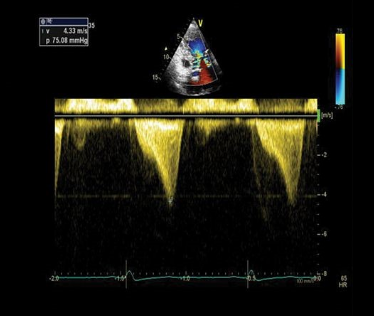

A point-of-care ultrasound was performed to evaluate for potential etiologies of syncope. The ultrasound displayed biventricular and interventricular septal hypertrophy (Figure 2), systolic anterior motion of the mitral valve (SAM, Figure 3), and a “dagger-like” continuous wave Doppler waveform emerging from the left ventricular outflow tract. (LVOT, Figure 4)

Figure 4. Apical 5-chamber view using continuous wave Doppler displaying a “dagger-like” left ventricular outflow obstruction with a maximal peak gradient of 75 mmHg.1

The left ventricular outflow tract (LVOT) gradient is another way bedside ultrasound can be utilized in the diagnosis of obstructive HCM. This is performed by placing the continuous wave Doppler beam over the LVOT in an apical 5-chamber view. A gradient > 30 mmHg is defined as intraventricular obstruction. About 1/3 of patients with HCM have gradients > 30 mmHg at rest, another 1/3 have it with provocation (Valsalva/exercise/medication), and 1/3 have no obstruction.11 In the ED, a Valsalva maneuver is an imperfect (underestimates exercise-induced obstruction) but convenient provocation. Furthermore, a gradient of > 50 mmHg is considered hemodynamically significant, often requiring invasive septal reduction therapies.12 Continuous Doppler images will classically show a “dagger-like,” late-to-rise waveform characteristic of HCM.